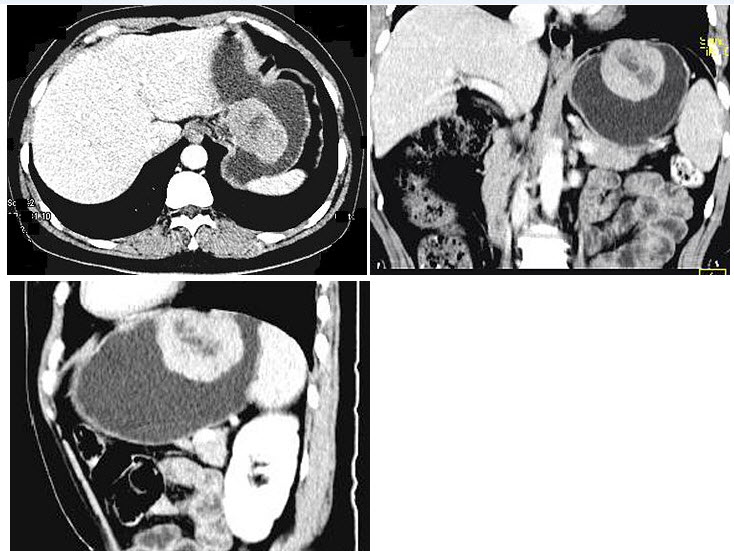

25、单项选择题

肝右前叶病灶,结合图像,最可能的诊断是()

A.肝血管瘤破裂

B.肝血管平滑肌瘤破裂

C.肝癌并破裂